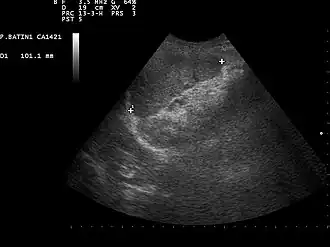

![]() Ultrasound image of a normal spleen that may be seen in part of the eFAST  | |

- Left upper quadrant of the abdomen (perisplenic view). Left upper quadrant is examined by working your probe down the midaxillary line starting at the left 8th rib to the 11th rib. This examines for free fluid around the kidney and spleen.